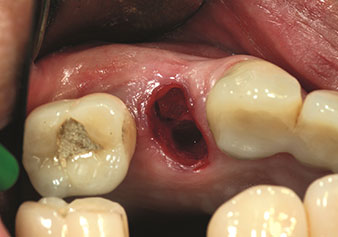

W&H also offers the perfect solution for the internal sinus lift.

Following preparation of the maxillary sinuses with the corresponding instrument set (Fig. 3), the new Z35P instrument (Fig. 4) is used to lift the membrane hydrodynamically. The same instrument set can also be used for piezosurgical preparation of the implant bed in increasing diameters (Figures 3 and 4 included with the kind permission of Dr Mario Kirste, Frankfurt/Oder).

Preparation of implant bed with I4P instrument

Fig. 3: Preparation of implant bed with I4P instrument. Photo: © Dr Mario Kirste (Frankfurt / Oder)